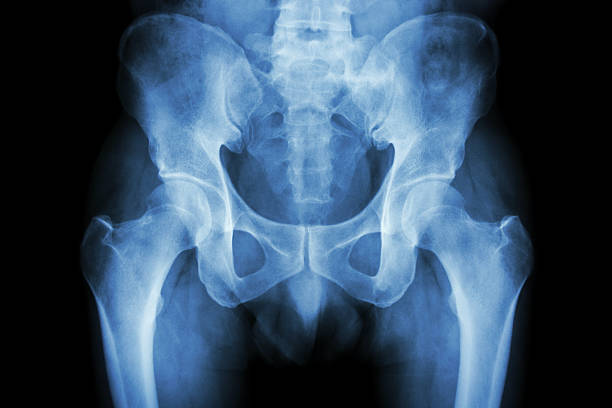

고관절은 걷기, 앉기, 서기 등 일상생활의 모든 움직임에 중요한 역할을 하는 부위입니다. 하지만 이 부위에 통증이 생기면 움직임이 크게 제한되고 삶의 질이 떨어질 수 있죠. 오늘은 많은 분들이 궁금해하는 고관절 통증 증상 10가지와 치료 정리에 대해 자세히 알아

보겠습니다.

고관절 통증은 단순한 근육통에서부터 관절염, 골절, 신경계 문제까지 다양한 원인으로 발생할 수 있습니다. 증상과 원인을 정확히 파악하는 것이 빠른 치료와 예방의 첫걸음입니다. 특히 고관절 통증 증상 10가지와 치료 정리를 통해 본인 상태를 체크해보는 것이 중요합니다.